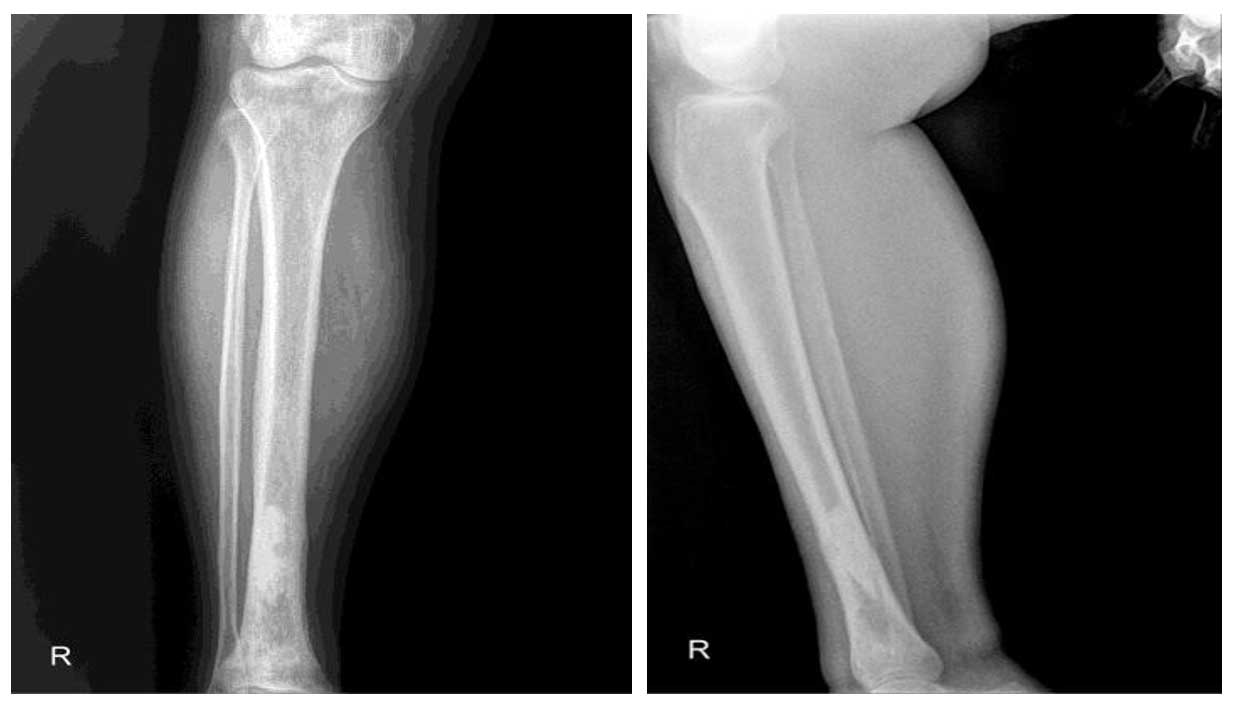

Ameliyat Öncesi: Röntgende distal tibiada düzensizlik görülmekte.